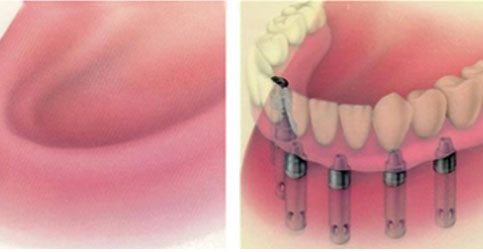

传统种植牙需要在缺牙处的牙槽骨内植入纯钛人工牙根,之后再等待3-6个月让人工牙根和骨头产生骨结合,再戴上牙冠,此时才能吃东西。这么算来,如果现在种牙,要赶在春节前可以用上咀嚼力强的种植牙吃饭,几乎是不可能了。

而像孟女士这样半口、全口的缺牙者,采取的是All-on-4即刻负重,半口缺牙只需在牙槽骨植入4颗植体,在当天戴上整排牙齿,恢复咀嚼力。将原本长达半年到1年的修复时期缩短到1天。不仅在戴牙当天可以吃饭,随着时间的推移,患者感到牙齿越来越有力。